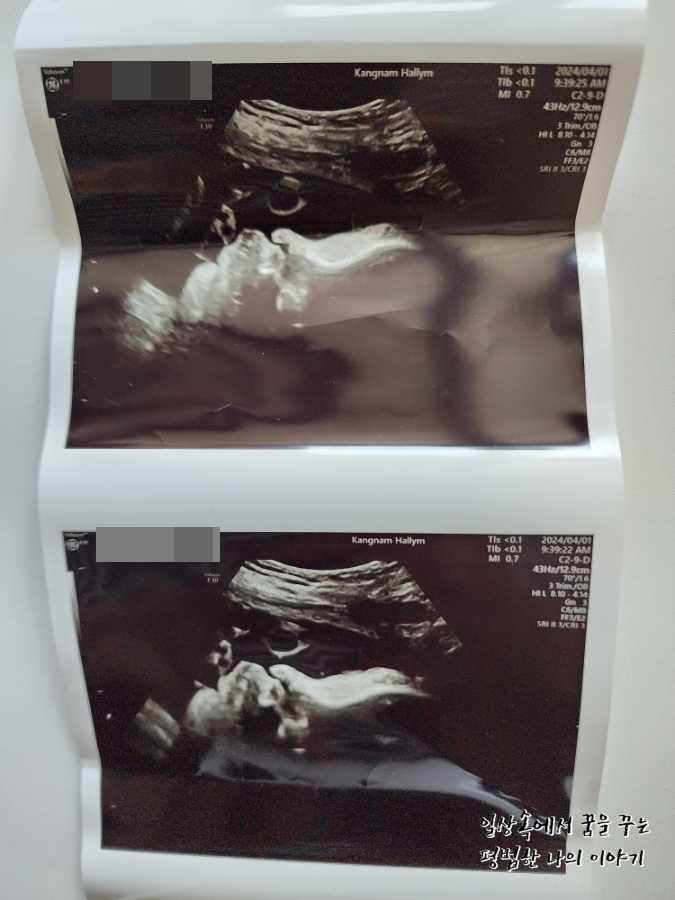

2024년 4월 1일(월요일)

BPD(Biparietal Diameter, 위에서 볼 때 태아 머리 단면의 가장 긴 길이): 9.33cm

HC(Head Circumference, 태아 머리둘레): 34.28cm

AC(Abdominal Circumference, 배 둘레): 36.6cm

EDD(Expected Date of Delivery, 출산 예정일): 2024년 4월 24일

FL(Femur Length, 허벅지뼈 길이): 7.34cm

GA(Gestational Age, 임신 주차): 36주 차 5일

EFW(Estimated Fatal Weight, 태아 예상 체중)=EBW(Estimated Body Weight): 3805g

FHR(Fetal Heart Rate, 심장박동 수): 142bpm

CL(Cervical Length, 자궁경부 길이): 정상

AF(Amniotic Fluid, 양수): 정상

원래 이번 주 목요일이 정기검진을 가는 날인데 이틀 전부터 계속 배가 생리통처럼 살살 아프고 아래쪽이 묵직하면서 뻐근한 게 심상치 않아 오늘 병원을 갔다. 지난번 방문보다 많이 커있지 않기를 바라며 방문했지만 아니나 다를까 지난번에 비해 거의 550g 정도가 늘어 이제 3.8kg에 육박하는 것이 아닌가. 첫째 39주 차 때와 비교하니 사이즈가 비슷하다.(머리둘레, 배 둘레, 허벅지뼈 등) 의사 선생님이 지난번 방문 때까지만 해도 최대한 39주 이후에 유도 분만 날짜를 잡는 게 어떠냐고 하셨었는데 이번 방문에서는 아무래도 4월 11일 혹은 12일, 늦어도 15일 전에는 유도 분만 날짜를 잡는 게 낫겠다고 하셨다. (그때면 38주를 살짝 넘긴 시점) 그러면서 제왕절개도 염두에 두고 있어야 할 것 같다고 하셨다. 머리 크기도 배 둘레만큼 차라리 커버리면 유도 분만할 때 괜찮은데 머리둘레가 배 둘레만큼이나 큰 편이 아니라서 나오다가 어깨나 배에 걸려서 탈골이 되거나 난산이 될 수도 있다고 하시더라. 그렇다고 자연분만을 포기하고 아예 제왕절개로 결정하기에는 첫째도 자연분만으로 잘 낳았고 회복도 빨랐기에 아쉬움이 남으니 우선 다음 주 월요일에 마지막으로 검진을 하고 결정하자고 하셨다. 첫째가 우량아여서 둘째도 우량아겠거니 했지만(막상 지금 20개월 첫째는 우량아가 아님, 그냥 평균적으로 크고 있음) 이렇게까지 클 줄이야 상상하지 못했다.